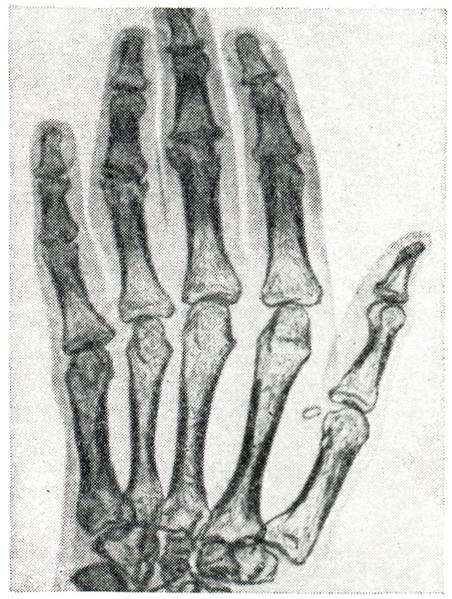

При микроскопии суставного хряща наблюдается его разволокнение, очаги некроза с образованием дефектов хрящевого покрытия и узурированием кости. Дефекты хряща замещаются грануляционной тканью, наползающей на суставную поверхность в виде различной толщины пленки (паннуса) — паннозный артрит. (рис. 2 и 3).

При паннозном артрите в субхондральных отделах кости наблюдается перестройка, сопровождающаяся разрастанием эндоста и формированием кист. Отмечается дальнейшее развитие остеопороза. Реже регистрируется уплотнение (эбурнеация) субхондральных отделов; нередко возникают краевые костные разрастания, характерные для деформирующего артроза. Эндостальные разрастания проникают в полость сустава с развитием в ней костной ткани. В исходе хронических форм серозного и серозно-фибринозного артрита могут образовываться фиброзные и костные анкилозы, чему способствует обездвиженность сустава, обусловленная резкой болезненностью.

При гнойном воспалении суставов морфологически может быть: 1) гнойный синовит, или эмпиема; 2) флегмона капсулы; 3) гнойный панартртп. В начальных стадиях гнойного синовита экссудат может быть прозрачным, однако вскоре он становится гнойным или гнойно-геморрагическим. При наличии анаэробной и гнилостной флоры в нем могут образоваться пузырьки газа (гнилостный артрит). Микроскопически в синовиальной оболочке от- мечается лейкоцитарная инфильтрация, очаги некроза и развитие грануляционной ткани, наползающей в виде паннуса на суставной хрящ (рис. 4). В суставном хряще очень рано обнаруживаются участки дистрофии и некроза. В дальнейшем развивается некроз и секвестрация значительных участков хряща, а при травматических артритах — даже целиком всей костно-хрящевой пластинки. Хрящевые секвестры вначале образуются в зоне контакта с воспаленной синовиальной оболочкой и паннусом, что связывают с протеолитическим действием лейкоцитов и абсорбционными свойствами грануляционной ткани.

Рис. 2. | ||

Рис. 3. | ||

Рис. 4. | ||